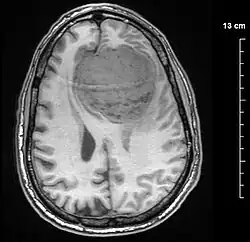

![]() | |

| An MRI of the brain, demonstrating the appearance of a meningioma | |

Meningiomas are visualized readily with contrast CT, MRI with gadolinium,[23] and arteriography, all attributed to the fact that meningiomas are extra-axial and vascularized. CSF protein levels are usually found to be elevated when lumbar puncture is used to obtain spinal fluid. On T1-weighted contrast-enhanced MRI, they may show a typical dural tail sign absent in some rare forms of meningiomas.[18]